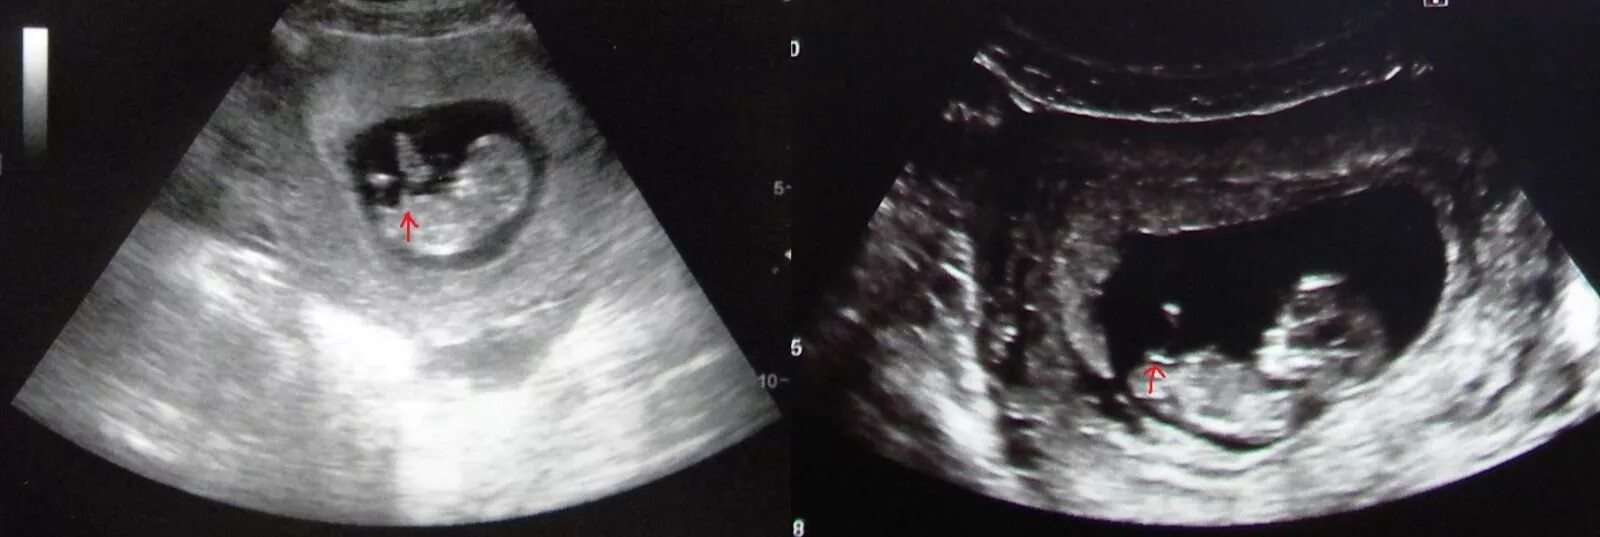

Узи шип